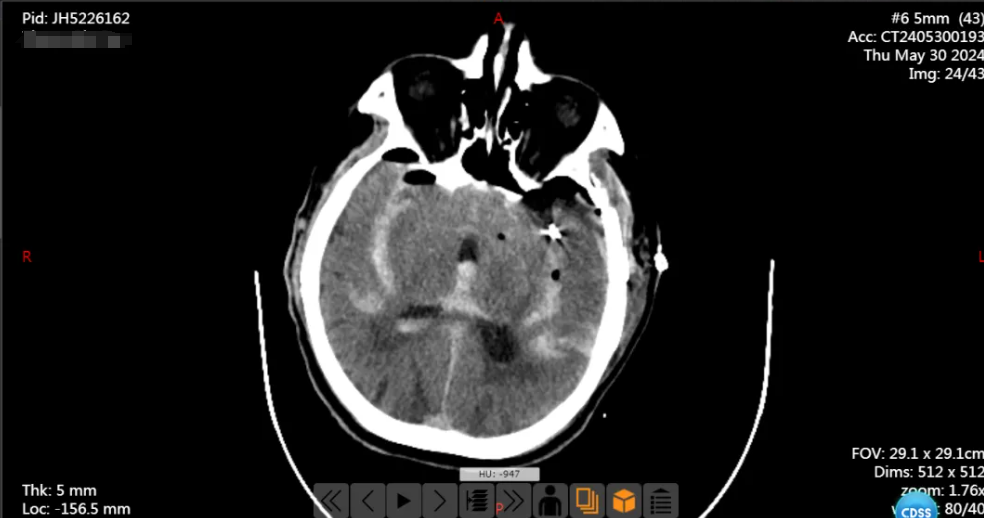

手术很顺利,术后患者安返病房,复查头颅 CT 提示左侧大脑中动脉瘤夹闭完全,载瘤动脉通畅,继续予以对症支持治疗。